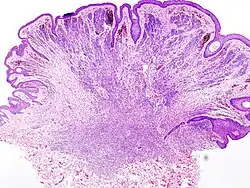

Ein Pigmentnävus (manchmal auch: Melanozytennävus oder melanozytärer Nävus) ist eine begrenzte, gutartige Fehlbildung der Haut, die im Gegensatz zu anderen Arten von Nävi aus pigmentbildenden Melanozyten oder verwandten Zelltypen besteht und daher meist eine braune oder bräunliche Farbe aufweist. Es gibt zahlreiche Unterarten von Pigmentnävi (siehe →Einteilung).

Epidermale melanozytäre Nävi und Junktionsnävi sind scharf umschriebene, braune Flecken im Niveau der Haut, während dermale melanozytäre Nävi eher breite, erhabene, weniger dunkle Gebilde darstellen, die über das Niveau der Haut hinausragen können. Auch dysplastische Nävi und Nävuszellnävi können erhabene Anteile aufweisen, bei letzteren abhängig von ihrer Entwicklungsphase: Mit der Zeit sinken Nävuszellnävi in die Dermis ab und führen so zu einer ausgeprägteren Erhabenheit. Auf einem Nävuszellnävus kann es zu einer Hypertrichose kommen.